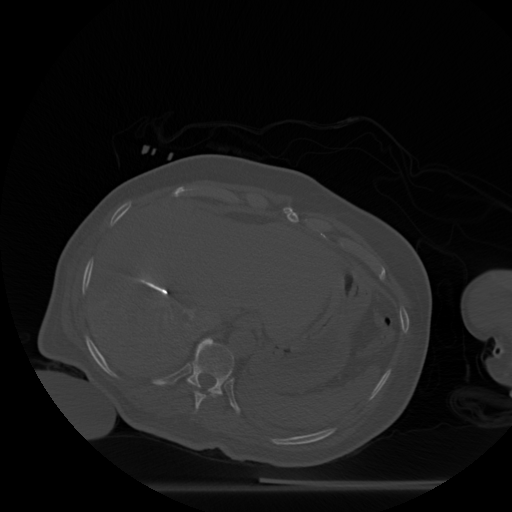

Figure 4: Goal: Track new changes. Reconstruction of slice 7 (‘test’) of Fig. 3 from only 90 views, using (b) Filtered backprojection and no prior resulting in streaks, the Structural Similarity Index Metric (SSIM) =0.48absent0.48=0.48 (c) CS and no prior resulting in blurred bone structures, SSIM =0.35absent0.35=0.35 and (d) unweighted global prior (slices 1-6 of Fig. 3 are used as templates) resulting in clear bone structures with less streaks, SSIM =0.55absent0.55=0.55. The region enclosed in red rectangle is our RoI as it contains both the new position of the needle and some background. All SSIM values are computed for this RoI.

Tracking the needle: We first choose slices 1-6 as our templates, and reconstruct slice 7 with the specific goal of tracking the needle and simultaneously reduce artefacts. Fig. 4 shows the reconstruction of slice 7 from its measurements from only 90 views. The reconstructions are quantitatively compared using SSIM.